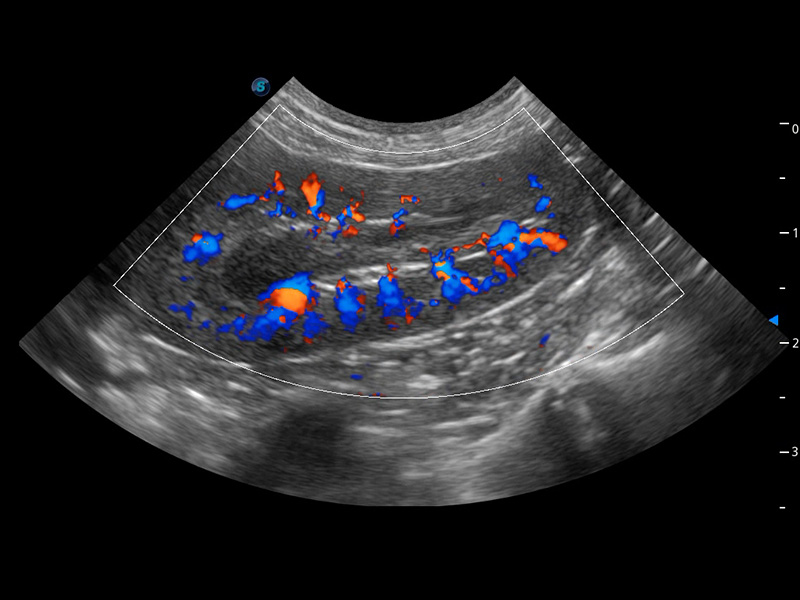

ProPet 60 作为一款高端台式动物超声设备,为动物医生的日常诊断提供了一系列贴合动物临床需求、解决临床实际问题的高级成像功能。凭借全系列高清探头,满足医生对腹部、心脏、生殖、浅表、肌骨等成像的所有需求,切实帮助您提升检查效率,提高诊断信心。

动物是人类最亲密的朋友和最值得信赖的伙伴。哈哈体育官网也一直致力于探索动物专用的超声影像解决方案。 全新推出的ProPet系列,是哈哈体育官网在动物超声影像智能化、专业化、精准化的一次跨越式革新。动物不能用言语来表述自己的不适,通过超声影像,ProPet系列搭建了动物医生与不同物种沟通的“桥梁”,为动物医生注入了“治愈之力”。